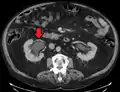

Peripelvic renal cysts may look like hydronephrosis on non-contrast CT (left image). However, CT urography (at right) reveals non-dilated calyces and pelvises.